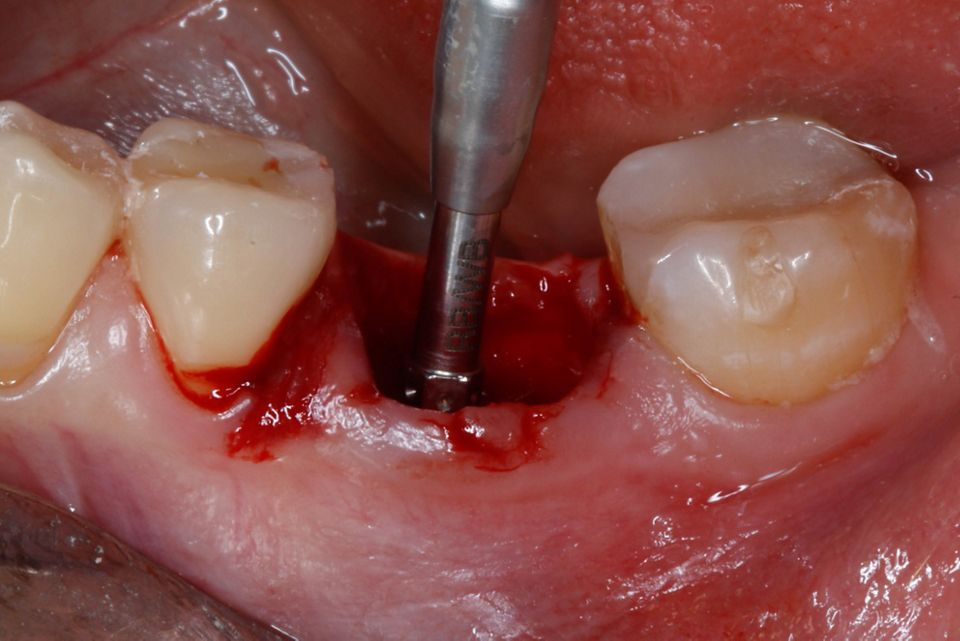

#36 牙的手术过程从局部麻醉和下牙槽神经阻滞开始。通过分割磨牙根实现无翻瓣反射的无创拔牙;从而保留肺泡壁和根间隔膜(图3-4)。仔细清洁牙槽,形成种植体路径并放置Straumann ® BLX 种植体 5.5 x 8 mm (图 5-7)。为了促进非浸没式愈合,将标准愈合基台连接至种植体。骨壁和种植体之间的间隙填充有同种异体骨材料颗粒(maxgraft®,botiss 生物材料,德国)。应用富含血小板的纤维蛋白(PRF)来实现适当的初步愈合。调整软组织边缘并用聚丙烯 6/0 缝合,使愈合基台暴露(图 8-9)。将粘性牙周Reso-Pac ®敷料(来自德国杜伊斯堡的Hager & Werken)放置在治疗区域上以协助愈合过程(图10)。